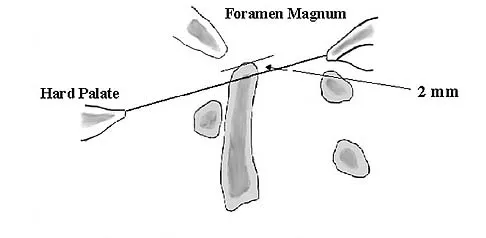

A 60-year-old woman with rheumatoid arthritis has atlanto-axial instability and basilar invagination. What MRI findings would suggest the need for cervical fusion?

The cervical medullary junction should be 135 degrees or greater. An angle of 125 degrees suggests compression of the cervical medullary junction. Other findings supporting surgical intervention include a cord diameter in flexion of less than 6 mm or less than 13 mm of space available for the cord. Clark CR (ed): The Cervical Spine, ed 3. Philadelphia, PA, Lippincott Williams & Wilkins, 1998, pp 700-701. Monsey RB: Rheumatoid arthritis of the cervical spine. J Am Acad Orthop Surg 1997;5:240-248.